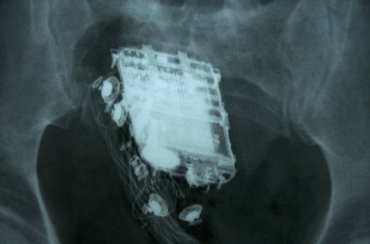

Raio-X mostra o telefone celular no reto de prisioneiro de 58 anos em Colombo, no Sri Lanka (Foto: AFP)